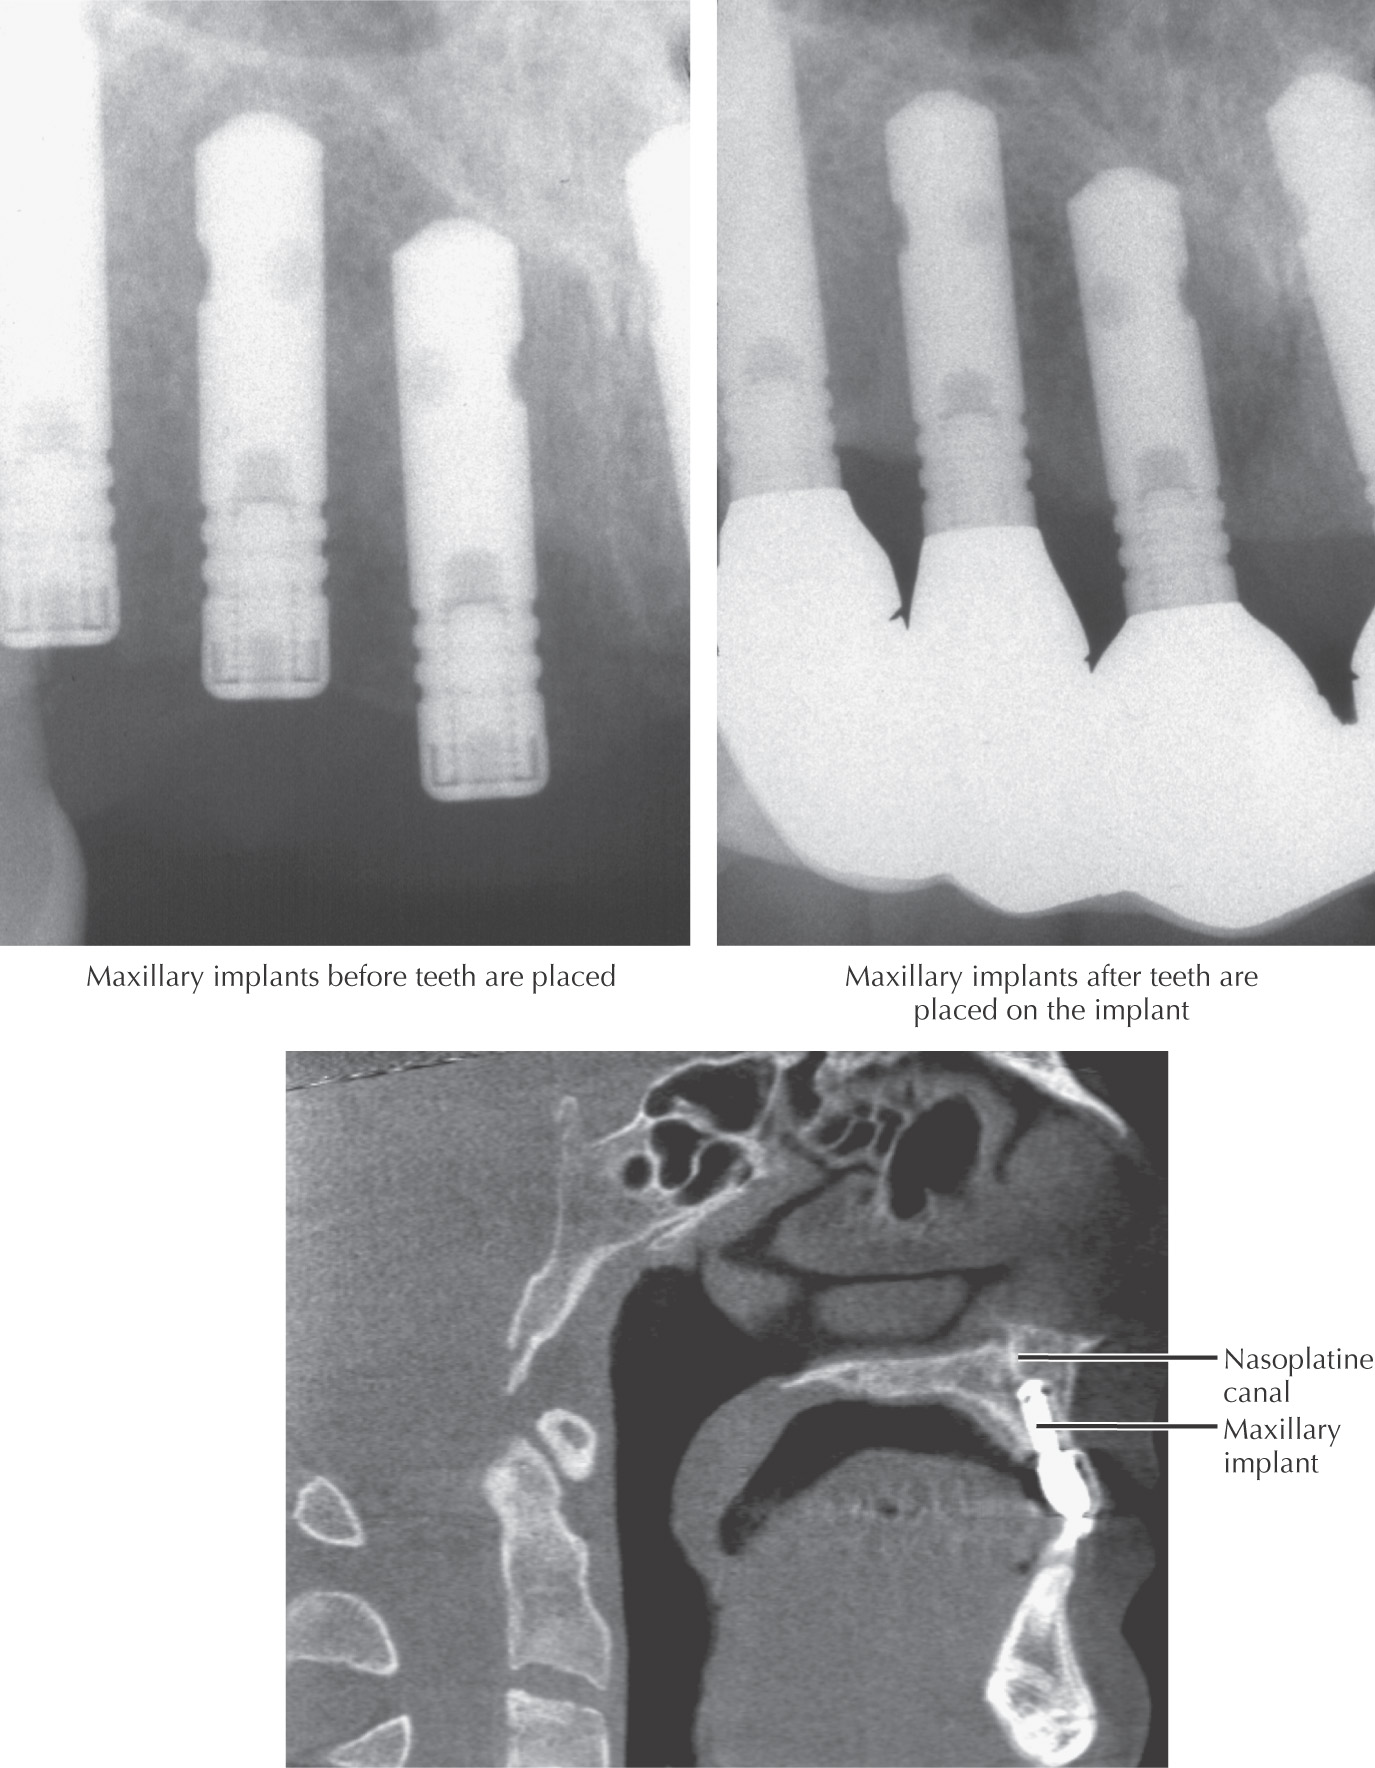

Common dental procedure to add fixed maxillary teeth to the oral cavity

Patient should be in relatively good health

Patient must have sufficient bone in a location suitable for placing an implant

It is becoming more common to use bone grafting before the surgical implant is placed

Bone grafts to provide adequate bed for implants may be harvested from the body or as allografts, or may be supplied as xenografts or synthetic bone substitutes